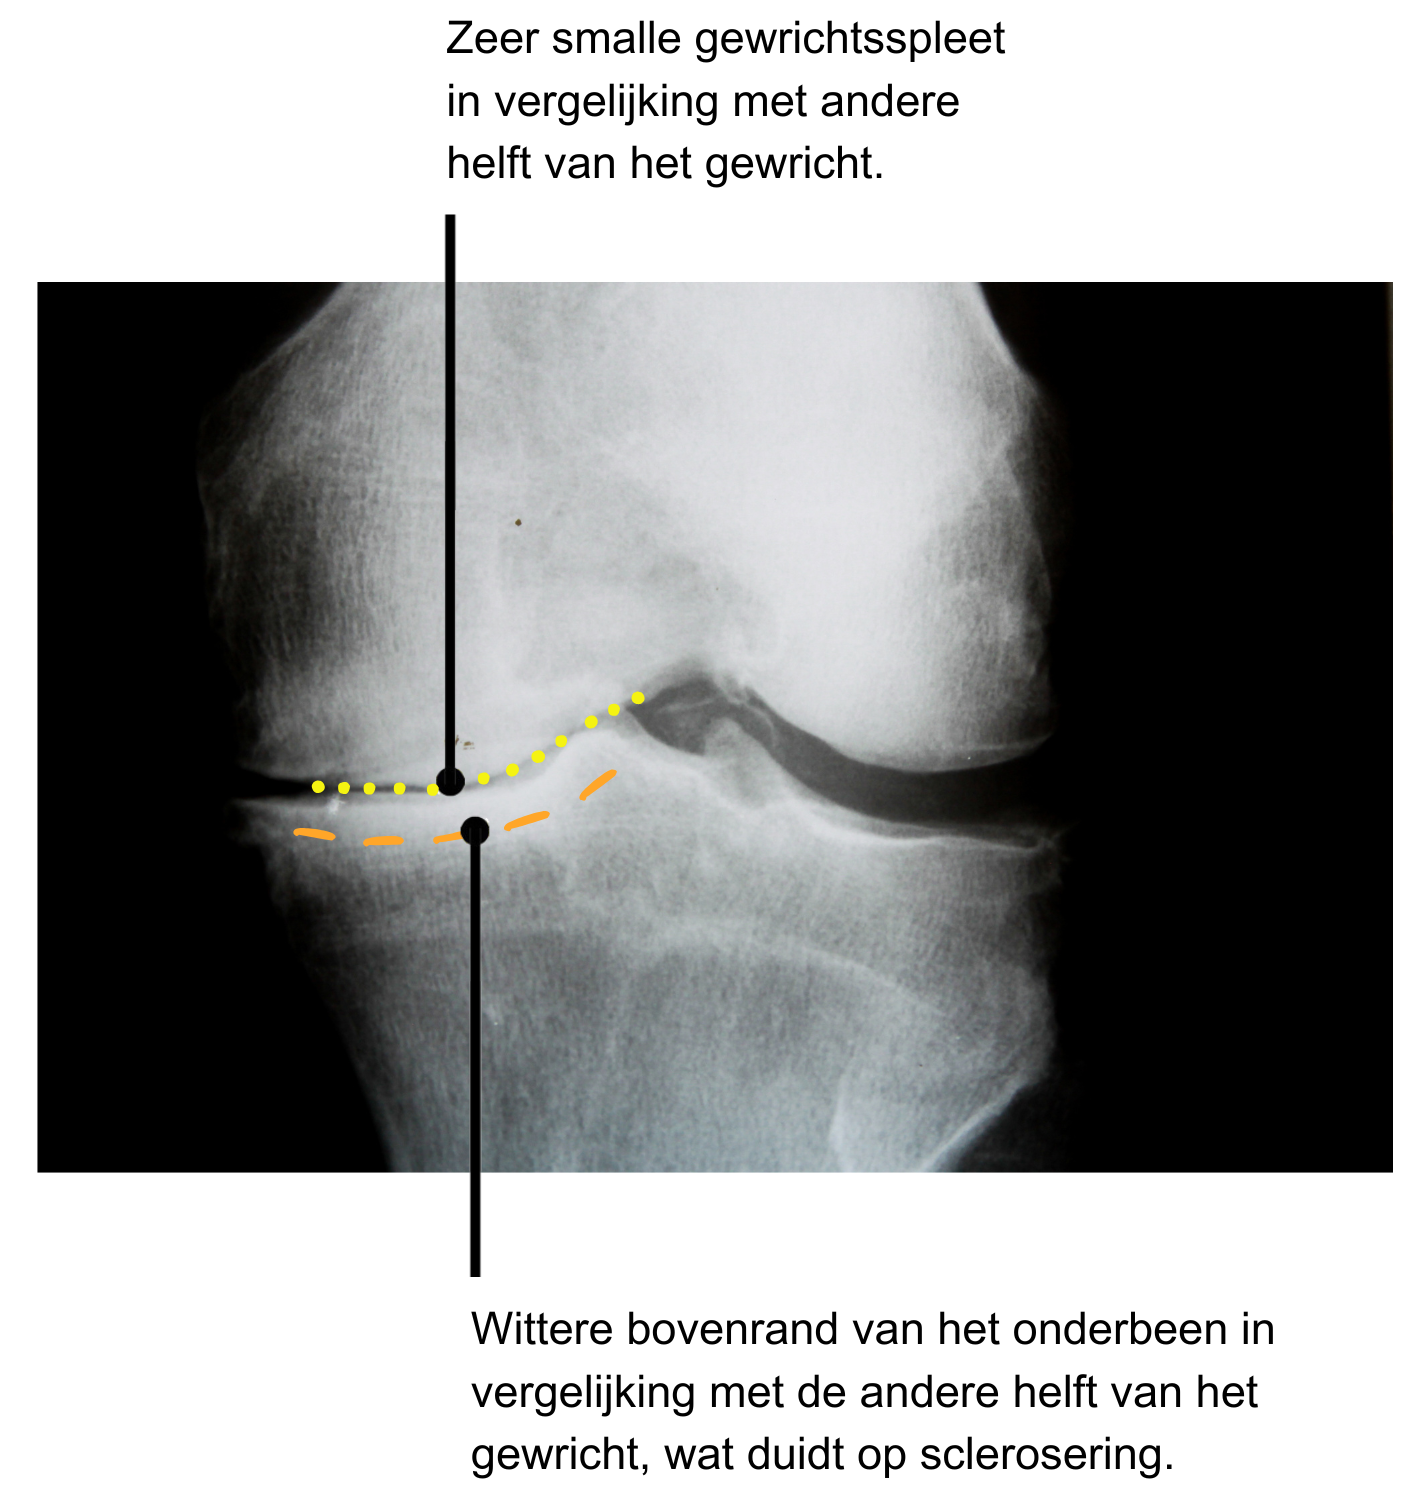

Een veelgebruikte methode om de ernst van artrose in beeld te brengen, is het classificatiesysteem van Kellgren en Lawrence (1). Hiermee wordt aan de hand van een röntgenfoto gekeken naar een aantal anatomische en fysiologische kenmerken van het gewricht. Op basis van deze kenmerken wordt de mate van artrose vastgesteld.

Orthopeden gebruiken deze gradering als hulpmiddel bij het maken van behandelkeuzes, zoals het wel of niet plaatsen van een prothese. Toch zegt de graad van artrose niet alles. Sommige mensen met een lage graad ervaren veel pijn en beperkingen, terwijl anderen met een hoge graad relatief weinig klachten hebben.

De beslissing voor een prothese is daarom nooit alleen gebaseerd op de röntgenfoto, maar ook op de mate van pijn, de functionele beperkingen en de persoonlijke wensen van de patiënt.

- Hoogteverlies van gewrichtskraakbeen

Gewrichtskraakbeen is niet te zien op een röntgenfoto. Wel kan de ruimte tussen de botstukken in een gewricht bekeken worden. Wanneer deze ruimte zeer klein is, of duidelijk kleiner is in vergelijking met je andere gewricht, kan er geconcludeerd worden dat het gewrichtskraakbeen in dikte is afgenomen. - De aanwezigheid van osteofyten

Dit zijn botuitsteeksels of botwoekeringen op de plek waar botweefsel beschadigd is geraakt. Als reactie op deze beschadiging produceert het lichaam extra botweefsel op de plek van beschadiging. Deze botuitsteeksels kunnen vervolgens ook klachten geven. - De mate van sclerosering van het subchondrale botweefsel

Dit is het verharden van het botweefsel dat zich direct onder het gewrichtskraakbeen bevindt. Normaal is het subchondrale botweefsel licht poreus om schokbelastingen op te vangen. Bij artrose kunnen hier verhardingen in plaatsvinden, wat ook klachten kan geven. - De vorming van cysten

Een cyste is een ophoping van vocht. Vochtophoping komt veel voor bij artrose. Een vochtstroming volgt altijd de weg van de minste weerstand en zal zich hierdoor uitbreiden in het gewricht. Hierdoor kan een uitpuiling ontstaan uit een gewrichtskapsel, een soort stevige zak om je gewricht heen. Zo’n uitpuiling wordt een cyste genoemd.